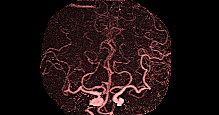

MRA collateral map: ‘DeepClue-Precise MR 측부혈류영상'

MR 혈관영상을 이용한 측부혈류영상

동맥기

모세혈관기

조기정맥기

후기정맥기

지연기